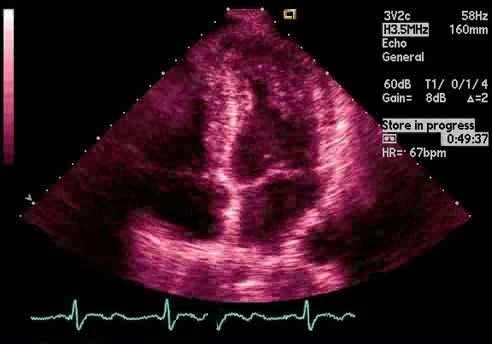

Эхокардиограмма при гипертрофии левого желудочка у спортсменов

Эхокардиография (ЭхоКГ) — это фундаментальный инструмент для обследования спортсмена с гипертрофией левого желудочка (ГЛЖ). ЭхоКГ предоставляет информацию, касающуюся величины ГЛЖ, ее характер и относительного увеличения толщины стенки ЛЖ по сравнению с полостью ЛЖ. Эхокардиограмма также используется для обнаружения и количественной оценки обструкции выносящего тракта ЛЖ, включая внутриполостные градиенты, измерения диастолической функции и продольной систолической функции. Наконец, ЭхоКГ играет важную роль в стратификации риска ГКМП.

Величина гипертрофии левого желудочка на ЭхоКГ

Что касается величины ГЛЖ, то у 1,5-3% белых спортсменов толщина стенки ЛЖ> 12 мм, но никогда не превышает 16 мм. Напротив, 13-18% чернокожих спортсменов имеют толщину стенки ЛЖ> 12 мм, но, опять же, не более 16 мм. Таким образом, независимо от этнической принадлежности, толщина стенки ЛЖ 16 мм и более у спортсмена указывает на патологию.

С учетом пола у белых спортсменок толщина стенки ЛЖ не превышает 11 мм. Для сравнения 3% чернокожих спортсменок имеют толщину стенки ЛЖ> 11 мм, но не более 13 мм. Белые спортсмены подростковой возрастной группы 14-18 лет очень редко обнаруживают ГЛЖ> 12 мм (0,6%), а когда это обнаруживается, это всегда лица в возрасте ≥16 лет с размерами площади поверхности тела взрослого человека. У 7% чернокожих спортсменов-подростков толщина стенки ЛЖ ≥ 12 мм, но не более 15 мм. ГЛЖ у чернокожих спортсменов-подростков регистрируется с 15 лет. Таким образом, можно обнаружить толщину стенки ЛЖ 14-15 мм у молодых черных футболистов в возрасте 15 или 16 лет без каких-либо других признаков сердечной патологии.

Картина гипертрофии левого желудочка на ЭхоКГ

Гипертрофическая кардиомиопатия - морфологически неоднородное заболевание, и возможна почти любая картина ГЛЖ. Наиболее частая картина - асимметричная гипертрофия перегородки примерно в 60% случаев, когда соотношение перегородки к задней стенке составляет> 1,3: 1. Почти у 10% пациентов ГЛЖ ограничивается верхушкой левого желудочка. Напротив, у спортсменов с физиологическим ГЛЖ наблюдается очень гладкая, однородная картина гипертрофии, которая не отличается на эхокардиографии более чем на 2 мм между соседними сегментами сердца.

Следовательно, наличие асимметричной гипертрофии перегородки или других неоднородных паттернов ГЛЖ свидетельствует о ГКМП и требует дальнейшего обследования. В нашем опыте обследования молодых спортсменов с ГКМП мы обнаружили, что у большинства из них асимметричная гипертрофия перегородки или ГЛЖ ограничиваются верхушкой. Только у 14% наблюдается однородная картина гипертрофии левого желудочка при измерениях толщины стенки ЛЖ 13-16 мм. У таких спортсменов дополнительная информация на эхокардиограмме может облегчить дифференциацию от физиологической ГЛЖ.

Гипертрофия левого желудочка относительно размера полости левого желудочка

Возможно, наиболее полезным эхокардиографическим наблюдением для дифференциации физиологической ГЛЖ от ГКМП является соотношение толщины стенки ЛЖ по отношению к размеру полости ЛЖ. В целом у спортсменов с физиологическим ГЛЖ увеличивается размер полости ЛЖ> 54 мм. Большой размер полости ЛЖ при нормальных показателях функции может успокоить спортсмена с гипертрофией левого желудочка, поскольку это скорее отражает физиологию, чем патологию. Однако наш опыт оценки спортсменов с ГКМП показывает, что, хотя полость ЛЖ> 54 мм является хорошим дискриминатором и поддерживает предположение о физиологической ГЛЖ, у 3% спортсменов с ГКМП наблюдается сочетание легкой концентрической ГЛЖ (13-16 мм) и полости ЛЖ > 54 мм.

Отношение h / R на ЭхоКГ является полезной объективной мерой этого отношения, где h — это сумма толщины перегородки ЛЖ и задней стенки в диастоле, а R - размер конечной диастолической полости ЛЖ. Спортсмен с соотношением h / R> 0,5 следует считать имеющим патологическую ГЛЖ.